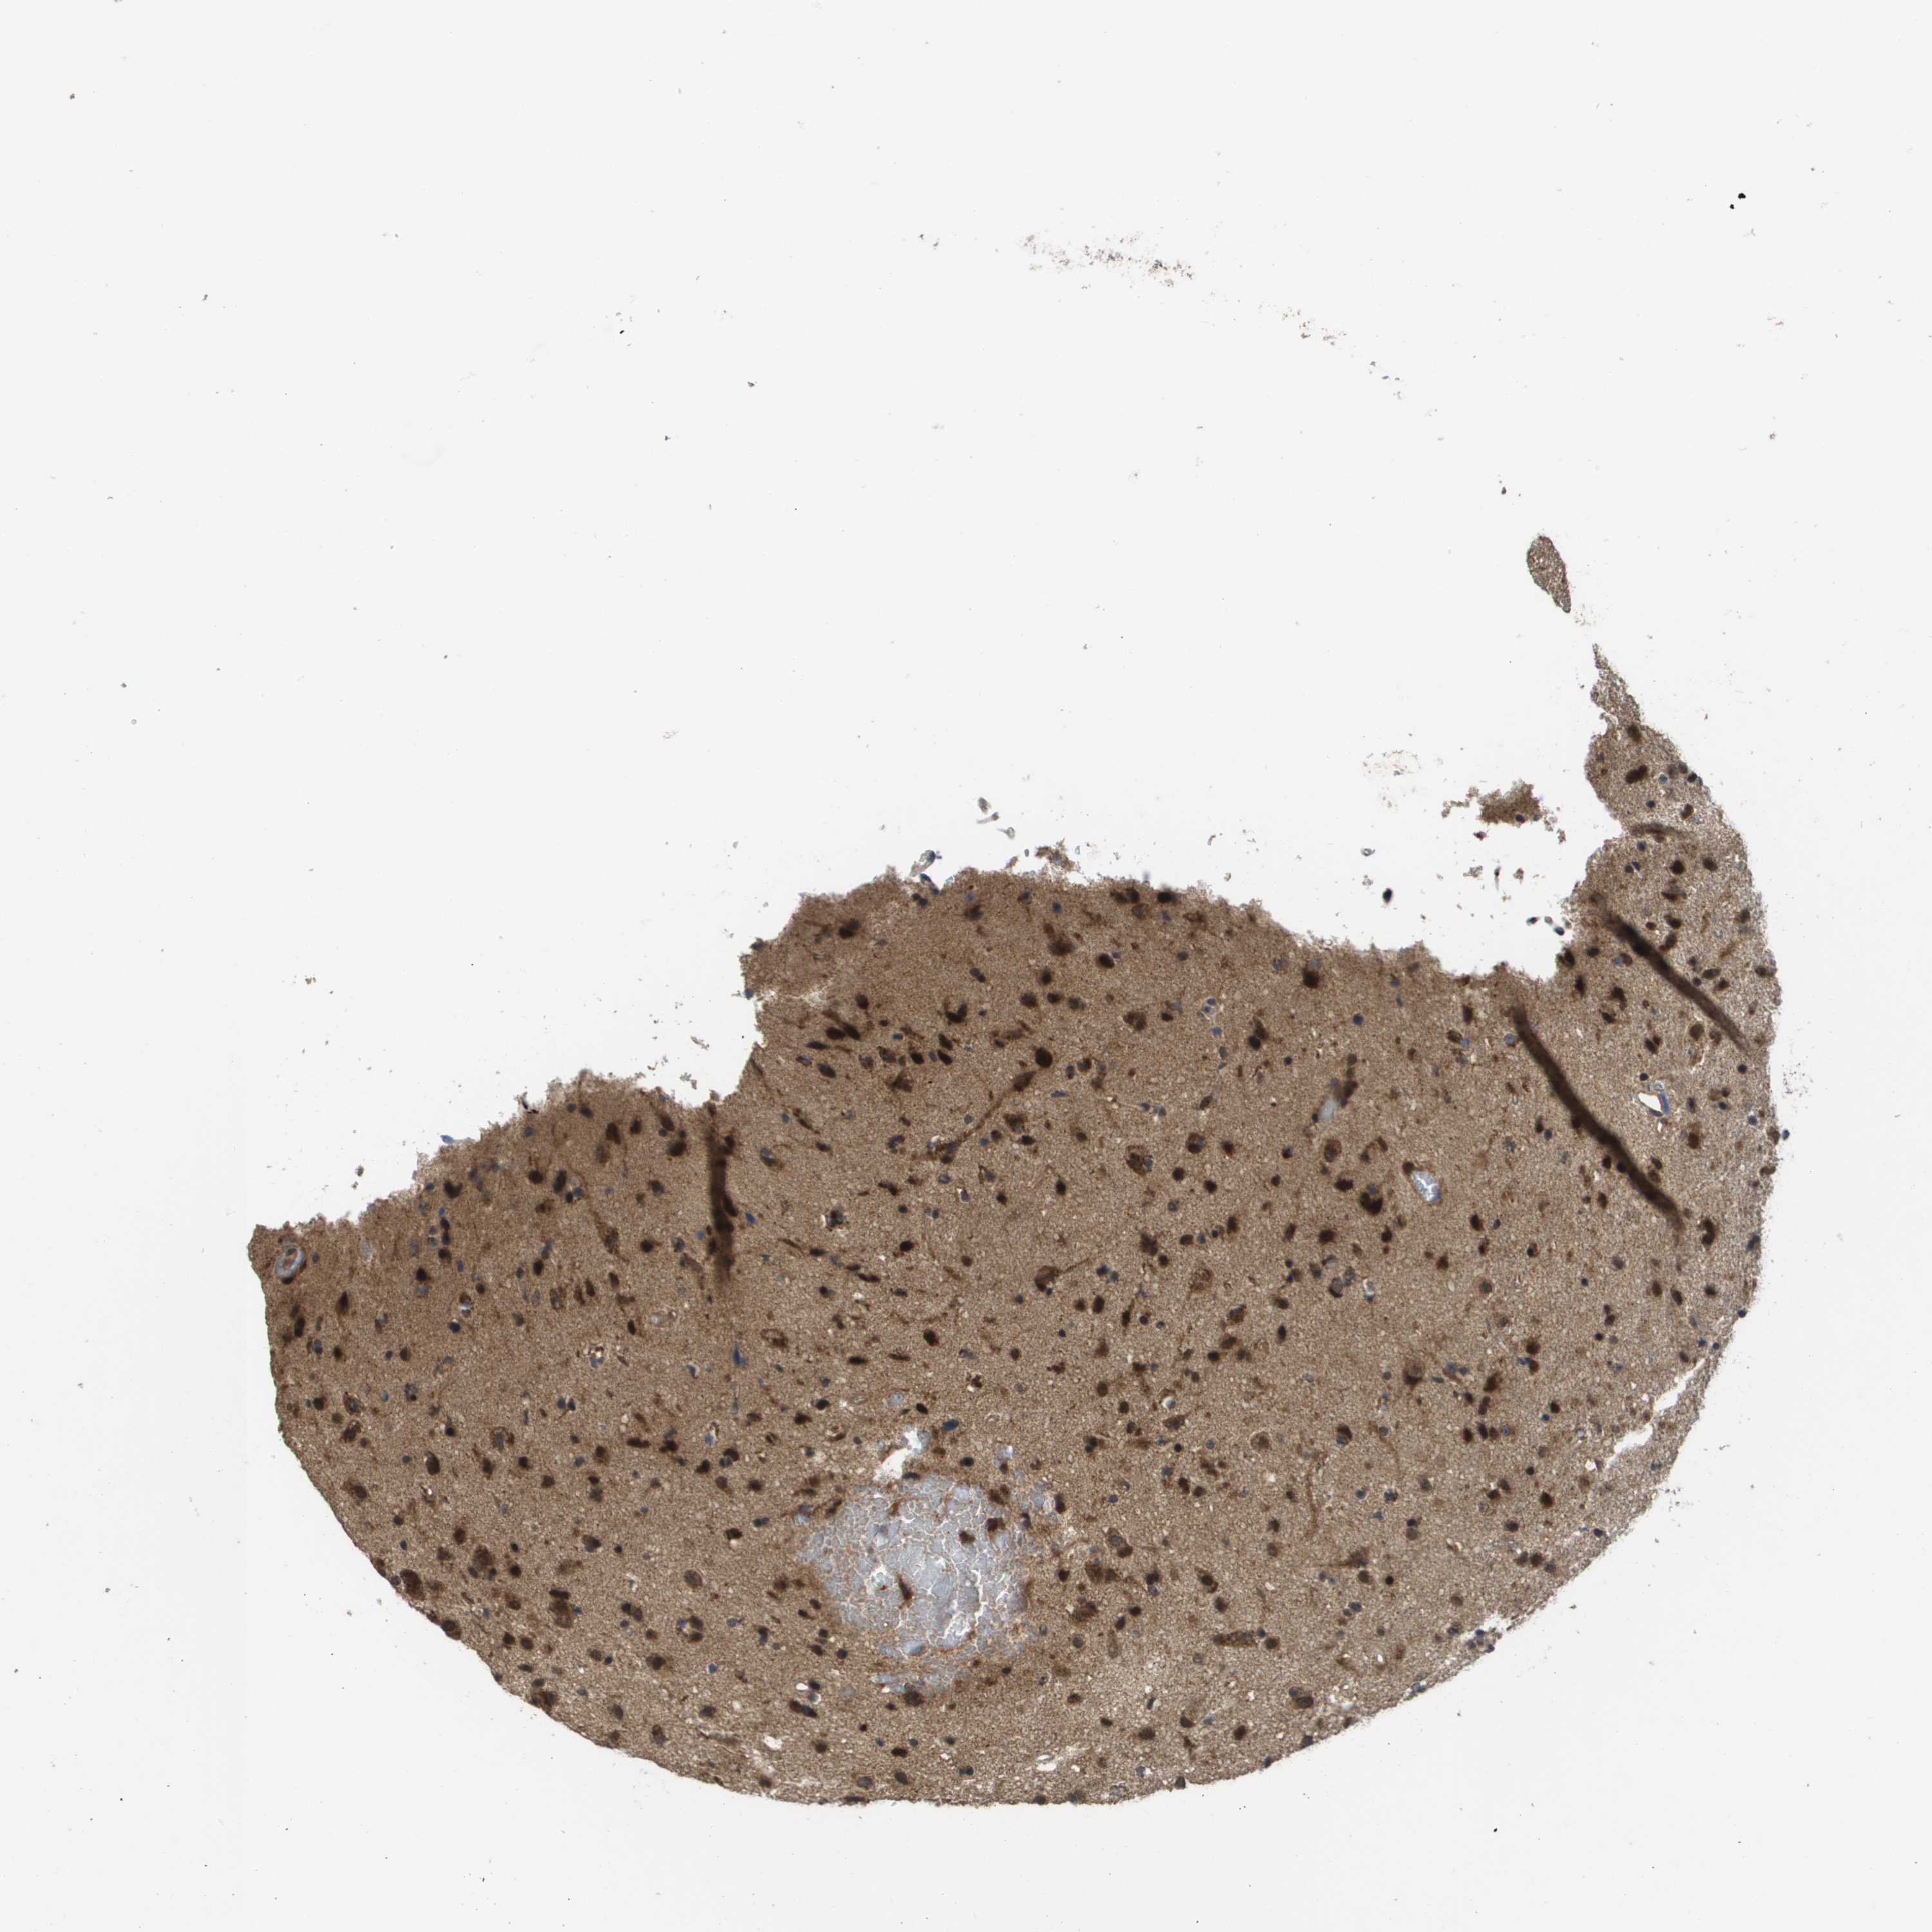

GLIOMA - Protein expressioni

A mouse-over function shows sample information and annotation data. Click on an image to view it in a full screen mode. Samples can be filtered based on level of antibody staining by selecting one or several of the following categories: high, medium, low and not detected. The assay and annotation is described here.

Note that samples used for immunohistochemistry by the Human Protein Atlas do not correspond to samples in the TCGA dataset.

Antibody stainingi

Antibody staining in the annotated cell types in the current human tissue is reported as not detected, low, medium, or high, based on conventional immunohistochemistry profiling in selected tissues. This score is based on the combination of the staining intensity and fraction of stained cells.

Each image is clickable and will lead to virtual microscopy that enables deeper exploration of all samples and also displays staining intensity scores, fraction scores and subcellular localization as well as patient and tissue information for each sample.

Antibody CAB017036

Staining

High

Medium

Low

Not detected

Intensity

Strong

Moderate

Weak

Negative

Quantity

>75%

75%-25%

<25%

None

Location

Nuclear

Cytoplasmic/membranous

Cytoplasmic/membranous,nuclear

Glioma, malignant, High grade

Glioma, malignant, Low grade